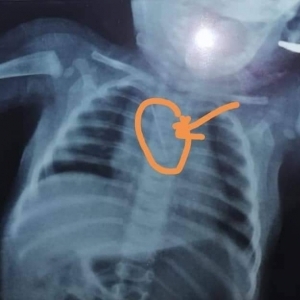

نجح أطباء قسم جراحة القلب والصدر بمستشفى بنها الجامعي في إنقاذ حياة طفل عمره 6 أشهر، كان يعاني من "كحة" مزمنة؛ إثر ابتلاعه دبوس طرحة من الحجم الكبير، ومستقر بالقصبة الهوائية.

وكان مستشفى بنها الجامعي استقبل طفلا عمره ٦ شهور وتم تحويله لقسم جراحة القلب والصدر يعاني من كحة مزمنة وأهله لا يعلمون السبب وبعمل أشعة عادية على الصدر تبين أن الطفل ابتلع دبوس طرحة من الحجم الكبير ومستقر بالقصبة الهوائية.

وعلى الفور، قام الدكتور محمد فؤاد، مدرس جراحة القلب والصدر، بعمل منظار شعبي صلب واستخرج الدبوس واطمأن أن النزيف توقف.